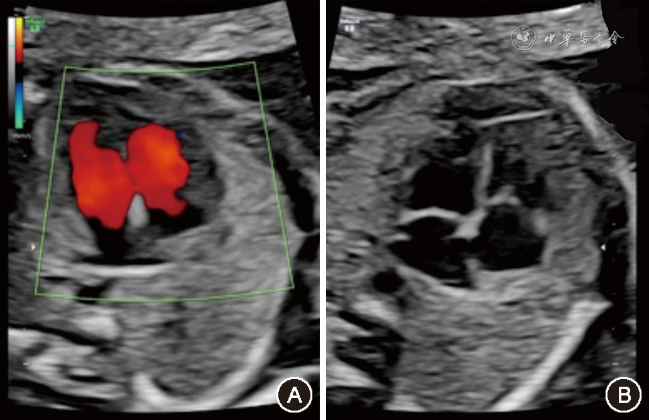

追溯患儿产前超声心动图未能检出三尖瓣下移畸形(图4),但胎龄38周+6时M型超声检查示胎儿心率快,283次/min,律齐,呈1∶1房室传导,VA间期短,诊断为室上性心动过速(图5)。